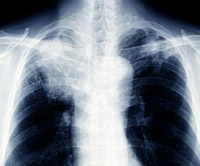

여성 폐암 환자가 전체 30%를 차지하는 가운데 생활 속 예방수칙을 숙지하는 것이 필요하다/사진=조선일보 DB

최근 폐암 여성 환자가 증가하고 있는 가운데 전체 폐암의 30%를 차지한다. 여성 폐암 환자의 경우 비흡연자가 대다수인데, 발견이 어렵고 사망률이 높은 치명적인 선암이 대부분인 것으로 나타났다. 이대목동병원 폐암센터장 이진화 교수의 도움말로 여성 폐암 예방을 위한 생활수칙을 알아본다.